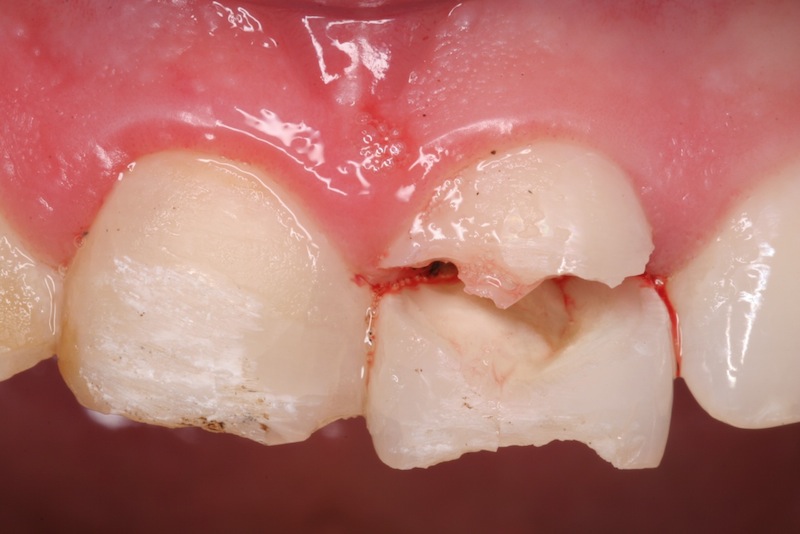

Bei der Therapie von Zahnfrakturen stehen aus endodontischer Sicht vitalerhaltende Maßnahmen im Vordergrund. Zähne mit nicht abgeschlossenem Wurzelwachstum können so ihr Wurzellängen und –dickenwachstum fortsetzen. Aus restaurativer Sicht gilt es Funktion und Ästhetik möglichst optimal wiederherzustellen. Die restaurative Versorgung von Kronen- Wurzel-Frakturen ist durch die subgingival liegenden Defektgrenzen massiv erschwert. Zur Defektdarstellung und Herstellung der biologischen Breite bieten sich verschiedene Alternativen an. In vielen Fällen ist eine kieferorthopädische oder chirurgische Extrusion ein sinnvoller Weg im Sinne der Zahnerhaltung.